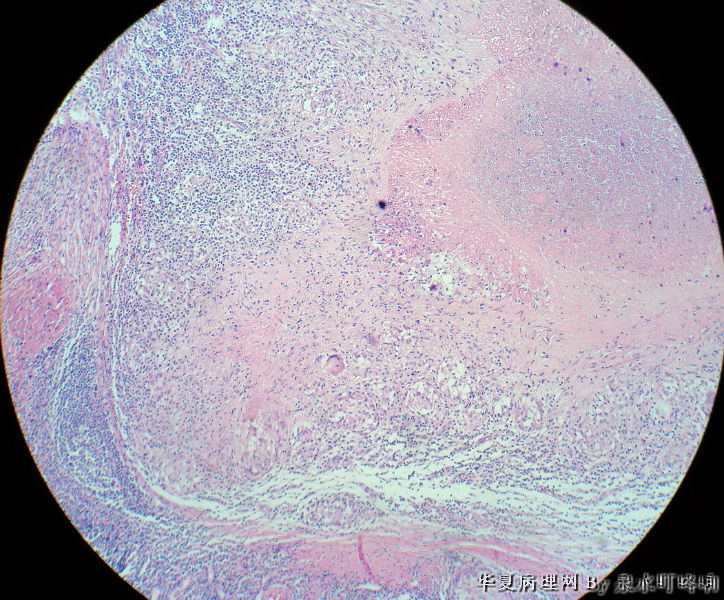

女,3岁,主因左腋窝肿物半年,术中见为肿大淋巴结,淋巴结内有脓液及坏死组织。

大体:灰红色组织一块,大小约4.6×3.5×2厘米,切面可见两个囊性区域,内容乳白色浓稠液体。